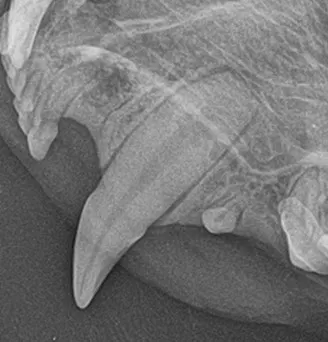

In cats, canine teeth are nearly cylindrical (root is not wider; A), so simple elevation may be sufficient, particularly if the tooth is already mobile due to chronic alveolitis or osteitis in older cats. In these cats, the gingiva may be very thin, making full-thickness mucoperiosteal flap creation challenging. In most dogs, however, the diameter and width of the root is broader than the widest part of the crown at the neck of the tooth, with a larger dimension from front to back (mesial to distal) than side to side (buccal to palatal; B). A full-thickness pedicle mucogingival flap with alveolar bone removal is recommended for both species but is more critical in dogs.

A